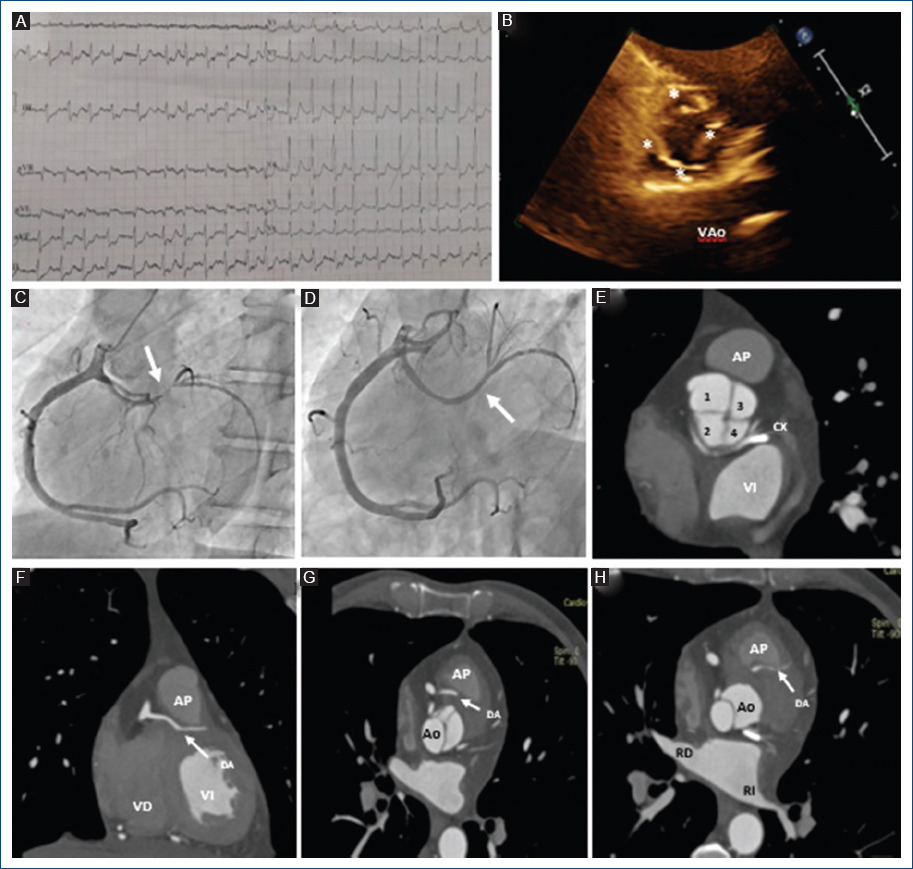

Hombre de 64 años que acudió a urgencias por presentar dolor precordial opresivo, intensidad 9/10, irradiado a ambos brazos, cuello y mandíbula. Se realizó electrocardiograma, el cual presentaba datos de enfermedad multivascular vs. oclusión de tronco coronario izquierdo (Fig. 1A). Igualmente se solicitaron niveles de troponina I ultrasensible con primera determinación en 627 pg/ml y control a las 2 horas en > 50,000 pg/ml, decidiendo ingreso a sala de hemodinamia por diagnóstico de infarto agudo de miocardio sin elevación del ST. Durante el procedimiento no fue posible canular ostium coronario izquierdo, decidiendo canular ostium coronario derecho, evidenciando arteria coronaria única (ACU), la cual se trifurcaba, observando coronaria derecha (CD) y descendente anterior (DA) sin lesiones significativas, y circunfleja (CX) con lesión suboclusiva proximal, colocando un stent de proximal a distal (Fig. 1 B y C). Se realizó ecocardiograma que reportó fracción de eyección del ventrículo izquierdo 56%, hipocinesia anterolateral basal y medio, hipocinesia anterior medio y distal e hipocinesia inferolateral basal y medio, además de válvula aórtica cuadricúspide (Fig. 1 D). Se solicitó angiotomografía computarizada (angio-TC) coronaria, confirmando ACU con trayecto interarterial de DA y retroaórtico de CX, así como válvula aórtica cuadricúspide (Fig. 1 E-H), realizando reconstrucción 3D (Fig. 2 A-D). El caso fue presentado en sesión médico-quirúrgica, decidiendo el egreso del paciente para continuar vigilancia por consulta externa.

Figura 1 A: electrocardiograma de 12 derivaciones, ritmo sinusal, frecuencia cardiaca 100 lpm, P 80 ms, PR 160 ms, aQR 120°, QRS 80 ms, QT 400 ms, con supradesnivel del ST de 2 mm en aVR e infradesnivel del ST de 4 mm en V1-V6, DII, DIII, aVF. B: angiografía coronaria. Arteria coronaria única con nacimiento en ostium derecho. Se observa lesión suboclusiva en circunfleja proximal (flecha). C: colocación de stent en circunfleja próxima-distal. Flujo TIMI 3 (flecha). D: ecocardiograma. Proyección paraesternal. Eje corto a nivel de grandes vasos. Se observa válvula aórtica cuadricúspide (diástole). E: angiotomografía coronaria. Se observa válvula aórtica cuadricúspide. F-H: angiotomografía coronaria. Trayecto interarterial de arteria descendente anterior (flecha).

Figura 2 Angiotomografía coronaria VRT. A y B: se observa ausencia de ostium coronario izquierdo, con presencia de arteria coronaria única con nacimiento en ostium coronario derecho de la cual emergen la coronaria derecha, la descendente anterior y la circunfleja. C y D: se observa curso retroaórtico de circunfleja y trayecto interarterial de arteria descendente anterior (flecha).